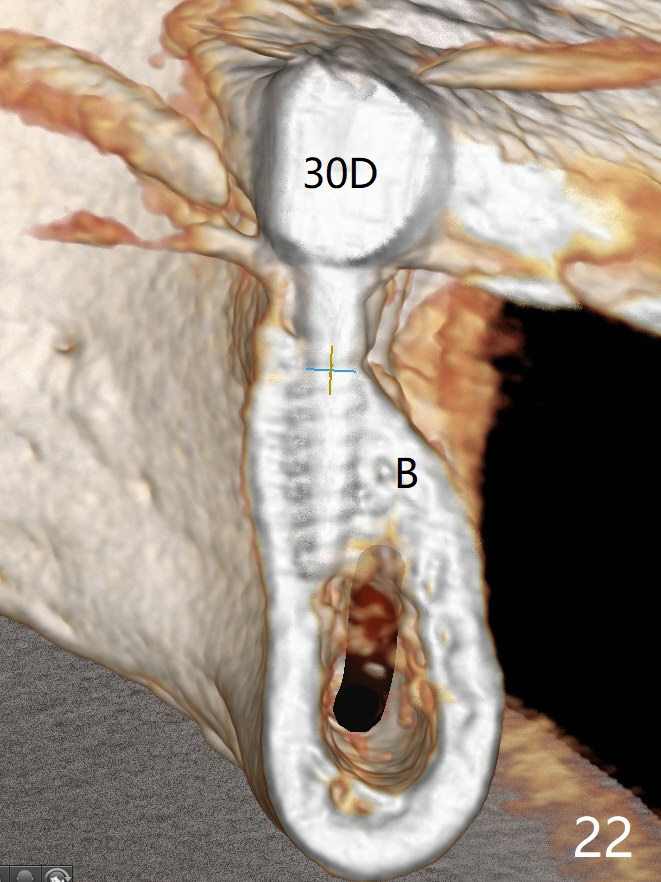

The edentulous ridge at #30 is narrow (Fig.1). After ridge reduction, osteotomy is initiated with 1.2 mm drill for 10 mm; the mesial osteotomy is to be changed (Fig.2 red line). Using a 1.2 mm drill placed in the distal osteotomy (Fig.3 D), the mesial osteotomy changes in trajectory with subsequent placement of a 2.5x10(4) mm 1-piece implant. Since the mesial implant is high in occlusion, the cuff of the distal implant is changed to be 2 mm (Fig.4 (shorter black line)). Panoramic X-ray is taken to show no violation of the Inferior Alveolar Canal (Fig.5 red dashed line). These two 1-piece implants are slightly lingually placed (Fig.6). The crestal bone around the implants resorbs without thread exposure 5 months postop (Fig.7). Impression is taken for a splinted crown (Fig.8-12). There is no metal show around the 2.5 mm 1-piece implants 6 months postop (advantage) vs. that at #28 and 29 (Fig.13). Bitewing is taken post cementation to determine whether residual cement is present (Fig.14). There is periodic swelling and pain in the lower right quadrant 2 years post cementation (Fig.15). In fact periimplantitis appears to have developed at #28 (Fig.16) with loss of the buccal bone (Fig.17,18). The buccal bone loss is less at #29 (Fig.19) and #20 (Fig.23) and no at #30 mesial and distal implants (Fig.20,21). A much smaller implant will be placed lingually at #28 immediate (Fig.24,25).